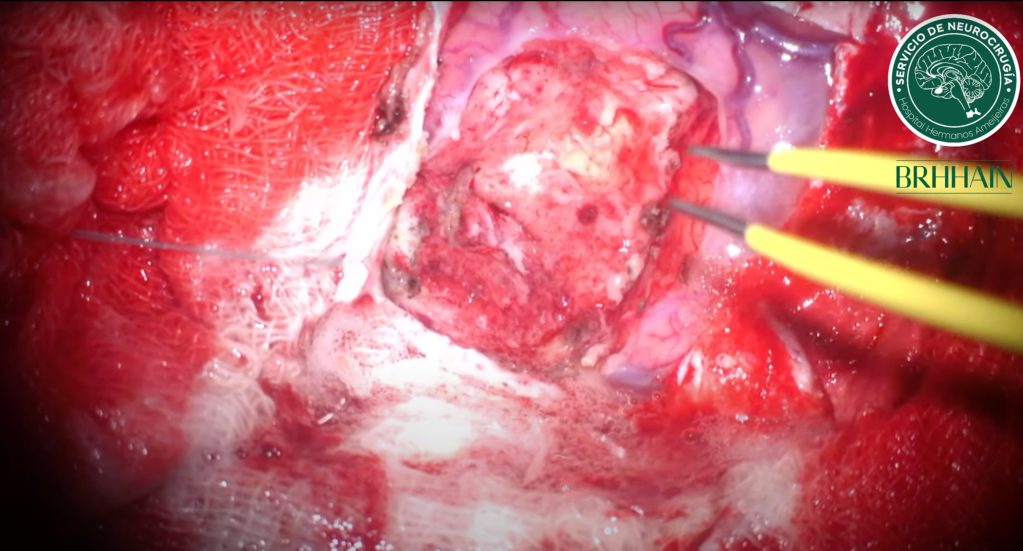

Innovación y videos de cirugía en acción

En este espacio, compartimos artículos científicos, avances en técnicas quirúrgicas y videos de operaciones que muestran un enfoque preciso, personalizado y humano en cada caso.

Nuestro objetivo es ofrecer soluciones efectivas para transtornos neurologicos que requieren tratamiento quirúrgico con un alto nivel de ética y profesionalidad.